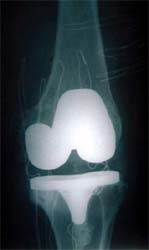

图:切除磨损破坏的关节面,安装平滑的人工关节面,组成新关节

为患者行一期双膝置换术,X线片显示假体位置好,下肢力线恢复。